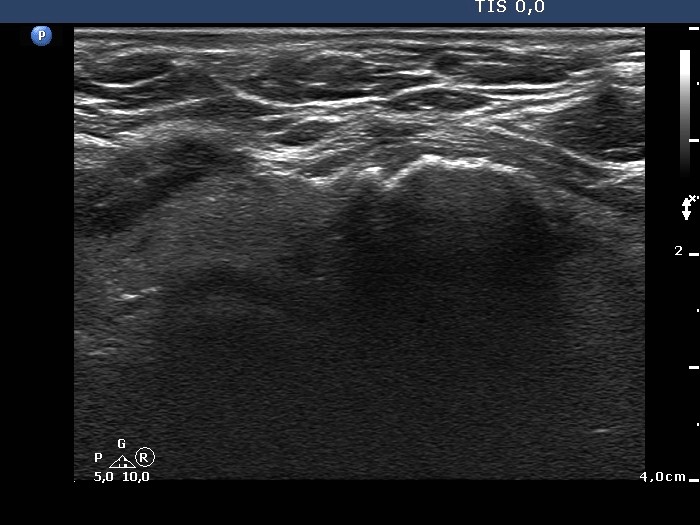

Benign colloid goiter (cytological diagnosis) |

There is a calcification in the dorsal part of the lesion.